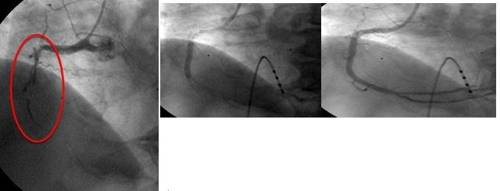

![(좌)심근경색 스텐트 시술 전 (가운데)스텐트 시술 (우)스텐트 시술 후 [강남세브란스병원 제공=연합뉴스]](https://img4.daumcdn.net/thumb/R658x0.q70/?fname=https://t1.daumcdn.net/news/201807/18/yonhap/20180718070021892jetl.jpg)

주로 혈관협착을 치료하기 위해 스텐트 삽입 및 풍선 확장술 위주로 시행되던 중재적 시술은 점차 적용 범위를 넓혀 이제는 인공 대동맥 판막을 이식하는 시술도 가능하게 됐다. 관상동맥 스텐트 및 경피적 대동맥 판막 치환술을 받고 건강을 되찾은 이씨가 대표적인 사례다. 경피적이란 말은 피부에 관을 넣어 목표물에 접근한다는 의미다. 피부를 절개하는 외과 수술과 달리 시술 후 큰 흉터가 없는 게 특징이다.

혈관 스텐트 시술은 약물이 방출되는 스텐트를 이용해 시술 후 재발을 막는 치료가 보편화 돼 있다. 시술 방법 또한 기존의 사타구니 대퇴동맥을 이용하는 것보다 환자가 더 편히 시술받을 수 있도록 손목의 요골동맥을 이용해 많이 시행된다.

예전에는 혈관의 석회화나 협착이 너무 심해 완전 폐색 상태가 되면 시술이 불가능했지만 최근에는 다이아몬드 드릴을 이용해 혈관의 석회를 갈아내고 시술하거나 완전히 막힌 혈관을 특수 와이어를 이용해 뚫는 시술의 성공률이 높아지고 있다. 50% 미만이던 완전 폐색 혈관 시술의 성공률이 최근에는 80% 이상으로 높아지면서 스텐트 시술의 적용 범위가 크게 확장됐다.